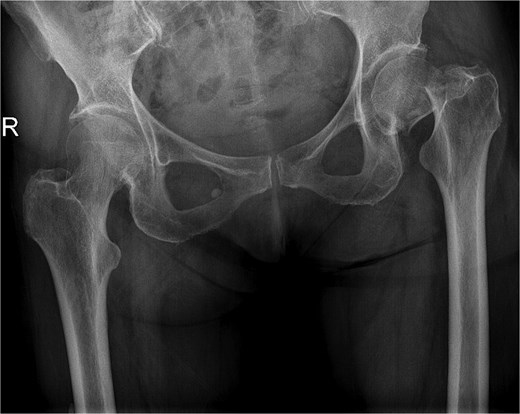

A 77-year-old female comorbid patient presented to the emergency department following a mechanical fall with acute displaced left femoral transcervical fracture (Fig. 1). Laboratory tests showed white blood cell count (WBC) count 11 800, C-reactive protein (CRP) 2.9, erythrocyte sedimentation rate (ESR) 18, and negative urine culture.

X-ray pelvis showing acute displaced and impacted left femoral transcervical fracture.